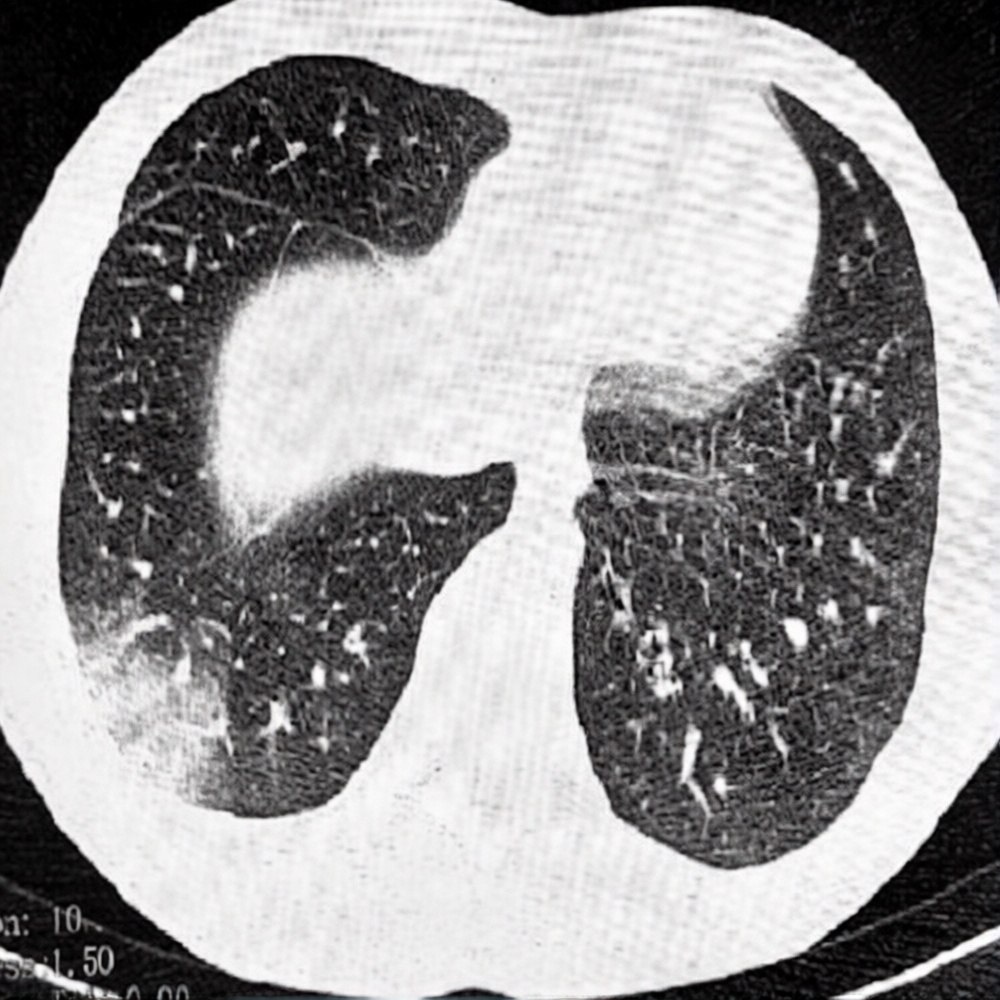

Кейс 1: пневмония, реанимация, ИВЛ

Крепкий мужик. Спортсмен. Начал парить — много, часто, постоянно. Итог: тяжёлая пневмония, реанимация, ИВЛ. Почти летальный исход. Выжил чудом.

До этого у человека не было ни пневмоний, ни похожих проблем, простудой болел редко. А тут — год активного парения, и лёгкие, по ощущениям, просто потеряли запас прочности. Он выкарабкался, но это было на грани.

Кейс 2: айкосы несколько лет — и рак лёгких 4 стадии

Тоже крепкий мужик. Спорт всю жизнь. Айкосы — пару лет, постоянно: до пробежки, после, в машине, на работе, дома, на отдыхе. Даже друзья говорили: «Ты перегибаешь».

Итог: больница, слабость, подозрение на пневмонию. Обследование — рак лёгких, 4 стадия.

Для всех это был шок. И для него — момент, когда всё стало ясно. Только, к сожалению, поздно.

Троих подростков с попкорновой болезнью лёгких экстренно увезли в реанимацию в Ростовской области после курения вейпов. У одного подростка развилась тяжёлая дыхательная недостаточность — ему потребовалась ИВЛ, второму сделали операцию на лёгких из-за вейп-ассоциированной пневмонии EVALI.

По словам врачей, жижки для вейпов содержат химикаты, которые разрушают дыхательные пути и вызывают воспаление лёгких.